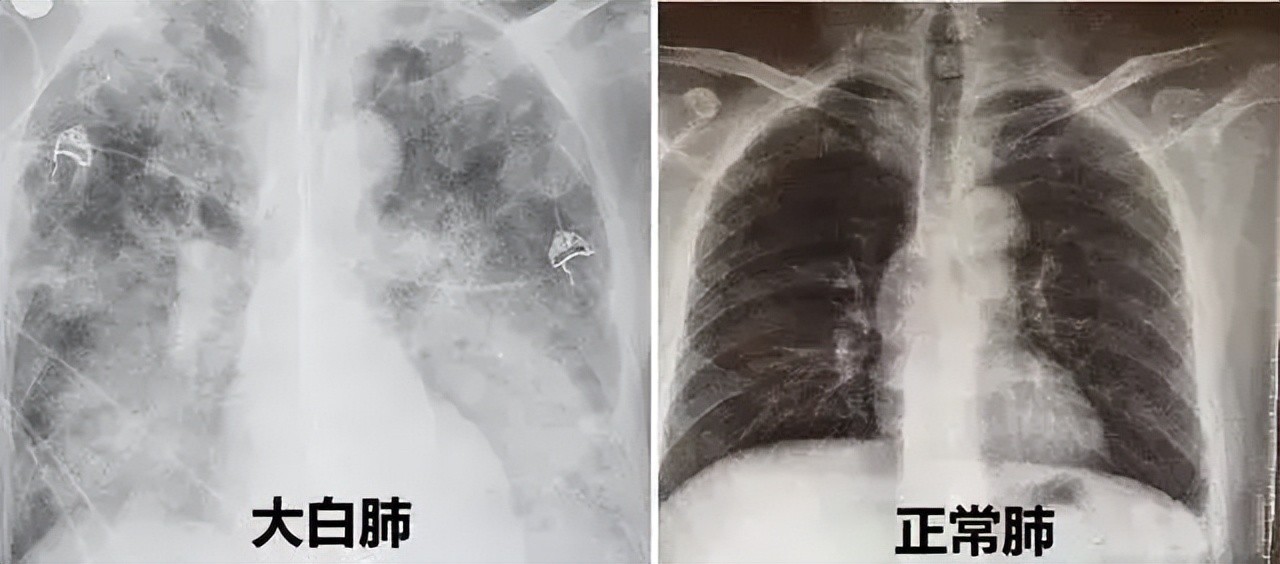

它是一种比较通俗的讲法,并不是说肺部真的变白了。

全称是急性呼吸窘迫综合征(ARDS),是患者在X光或者CT检查下,肺部显影呈一大片白色而得名,由肺部细菌感染或人体炎症反应所致。

健康的肺,在CT上显示应该是黑黑的,在CT片的透射下,很容易透过去,空气含量看起来很多。

而如果整个肺部看上去都是白的一片,那多半就是“白肺”。

(注意:不是出现炎症就都叫白肺,白肺属于比较严重的肺炎表现。一般白色面积达到70%-80%,在临床上口语化称为白肺。)